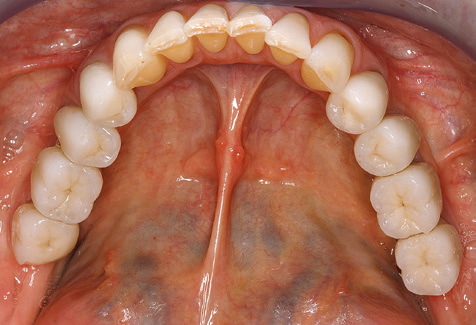

Standardised and regular risk-adapted care in the scope of SPT is the key to treatment success for the clinical long-term success in periodontically compromised patients. This is particularly true for patients fitted with implants following successfully completed periodontal treatment (Fig. 11a and b).

Before initiating the prosthetic treatment, it is advisable to inform the patient of the time and financial costs associated with the SPT (two to four SPT sessions per year for the rest of his/her life). This contributes significantly to ensuring the patient’s compliance. In addition, the practice is required to provide the rooms and staff necessary for the care of the periodontically treated patients.